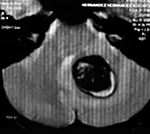

Paciente femenino de 29 años de edad con historial de cefalea crónica que presenta súbitamente disdiadococinesia y dismetría izquierda.

El estudio de RMN presenta una lesión bien circunscrita en hemisferio cerebeloso izquierdo con periferia de predominio hiperintenso en T1 y T2, y centro hipointenso, edema perilesional mínimo, así como una imagen de un vaso venoso alimentador que recorre hacia el ángulo pontocerebeloso izquierdo.

Se realizó una craniectomía suboccipital paramedial derecha, así como un abordaje transcortical en el hemisferio cerebeloso izquierdo llegando a la región perilesional de aspecto amarillento, posteriormente se observa una lesión oscuro-verdoso de contenido hemático antiguo, retirando la cápsula y su contenido en la totalidad.

La evolución clínica de la paciente fue satisfactoria solo preservando la dismetría como secuela.

El resultado histopatológico fue consistente en angioma cavernoso.

El estudio de control de RMN se observa la brecha quirúrgica y ausencia de lesión (figs. 1, 2 y 3).

Figura 2:

Cortes axiales en ponderación T1, cambios postquirúrgicos.